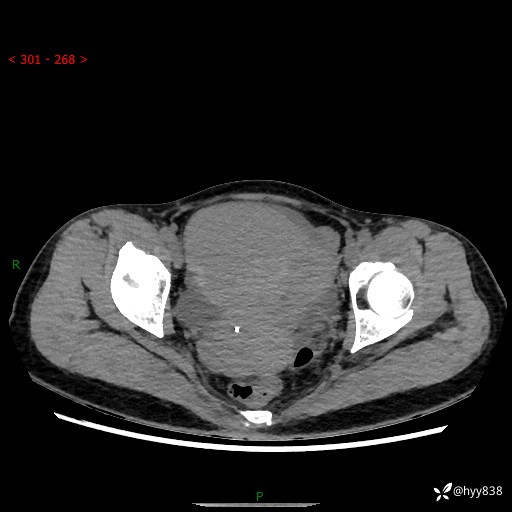

【患者信息】:女,50岁

【主诉】:外院超声发现腹盆肿块,为进一步诊治来我院,门诊已“盆腔肿块”收入院。

腹盆CT平扫+增强

【临床诊断】:盆腔肿瘤